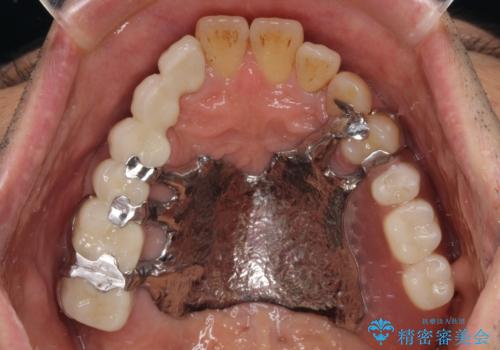

装着感の良い入れ歯を作りたい 金属床を使用した適合の良い部分床義歯

より適合の良い義歯とするため、セラミッククラウンなどは義歯の設計に合わせた土台の歯となるよう全て再製作をし、安定感に優れた義歯を製作することができました。